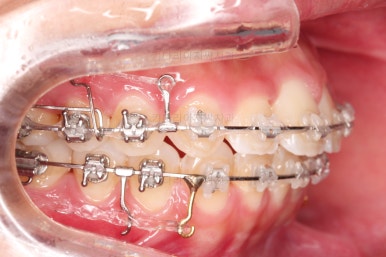

8개월째 사진입니다.

이제 약 4~5개월의 시간만 남았을 뿐입니다.

분명 처음보다는 좋아지고는 있으나 많이 아쉽습니다.

여기서 약간의 변화만 생기고 종료할 수 밖에 없다면,(물론 모두 수용하기로 하고 시작하였고, 환자분은 만족하실 수 있겠지만) 매우 아쉬움이 큰 치료였을 법 합니다.

일단 무조건 당깁니다.

1, 2, 3단계고 뭐고 디테일한 마무리고 뭐고 전부 동시에 진행합니다.

당기기-마무리 같이 진행하면서 할 수 있는 최선을 다해 뒤로 당겨줍니다.